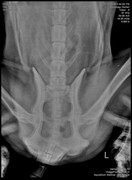

Добавлено (12.11.2018, 20:37) --------------------------------------------- Сил нет писать. Просто нет ни каких моральных сил. Нужно дойти до стадии принятия и жить дальше. Вот, что я узнала. при ортопедическом осмотре нарушений со стороны опорнодвигательного аппарата не выявлены. ( не считая старых травм, на кануне укол получил, поэтому не хромал). Рентген делали без миорелаксанта. Не хотела его "нагругжать". По ним вроде, тоже с суставами все ок. Есть подозрение на грыжу в отделе между последним кресцовым и первым хвостовым. Анализ мочи в норме, кроме кислой среды. На узи нашли наше старое новообразование. Оно немного меньше (на пол см.) . При ректальном осмотре простата совсем маленькая (около 1 см) (это потому что мы его кастрировали) Самое плохое, что на рентгене мы нашли еще одно новообразование. Оно давит и на мочевой и на кишечник и может быть причиной болей. С сегодняшнего дня у Цезаря подтекает моча. Если лежит на одном месте пару часов, лужа 20 см.образуется. Какал раньше 3 раза в день. Сейчас 1 раз. На сегодняшний день, колю мелбек и мильгамму. Аппетит хороший, бегает, по лестнице ходит. Если НПВС обезбаливает - это точно боль связанная с нервом, а не с новообразованием. Возможно он передавлен. Я пока не придумала, что делать???? Вообще..... Я точно знаю, что хочу как можно меньше страданий ему принести и переживаний. Он все эти клиники переносит с таким стрессом. Я хочу любить его и баловать. Но в то же время - я врач - и сидеть сложа руки не могу. Вот что я прошу! 1) может возможно снимки показать заочно Строку или еще кому-то в МИнске, послушать их! 2) если решать обезболивать, я за трококсил. Т.к. уезжаю и не смогу контролировать процесс. 3) дайте совет, кто сталкивался с подтеканием, с запорами из-за уменьшения просвета кишечника. Как вы справляетесь? Памперсы? Или что-то можно придумать? 4) Хочу услышать много мнений и все переварить. Но пока вот что я думаю. Цезарь мой родной человек. ТО есть лучше человека. И я не хочу последние его месяцы мучать , оставлять одного. Мне сейчас написали врачи - однозначно оперировать! Передавливает кишечник и может быть поздно.Но я не знаю.... я не хочу чтобы он умер на операционном столе или чтобы после операции было еще хуже. Я прошу совета!!!!!